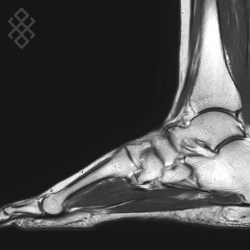

IRM du Pied/Avant-pied

Vous entrez dans l'aimant, ouvert des 2 côtés, les pieds en premier et allongé sur le dos avec les bras le long du corps. Pour recueillir le signal et construire les images, vous aurez le pied dans une antenne. Étant donné que cet examen est bruyant, vous aurez à votre disposition des tampons auriculaires pour atténuer le bruit de la machine.